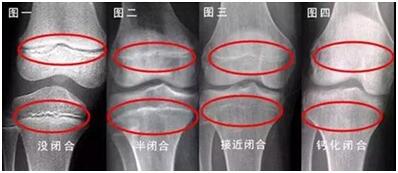

到暑期,各大医院儿科的生长发育专科就人满为患。据了解,这些就诊的孩子大部分都是因为身材矮小或有性早熟的症状就诊,其中也有一些生长发育正常的,家长特地带孩子到专科门诊检测骨龄。据专家介绍,骨龄是国内外公认能精确反映人体成熟度、骨骼生长状况的一个重要指标。根据孩子当前的骨龄,就可以预测出他还可能长多高。骨龄一旦闭合,身高将停止生长。一旦骨龄闭合就无法长高。